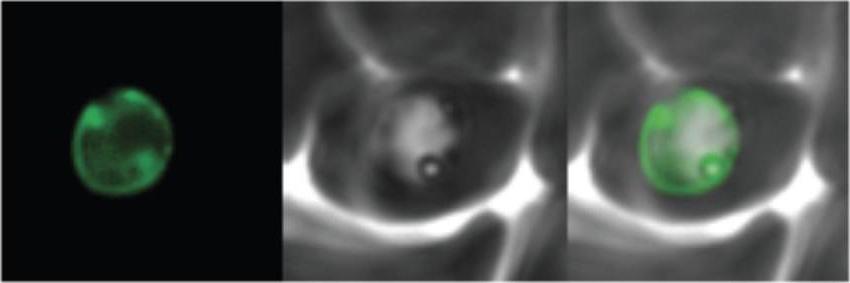

Imaging data (from Malaria Metabolic Pathways)

Localization of PfSUB3 in the parasite by immuno-fluorescence assay. Immunofluorescent staining of ring, trophozoite and schizont stage parasites with anti-PfSUB3 antibody. Cy3-labeled anti-mouse IgG was used as secondary antibody and nuclei were counterstained with DAPI. Cy3 fluorescence signals were seen in schizont stage parasites. PfSUB3 accumulates in the parasitophorous vacuoleAlam A, Bhatnagar RK, Chauhan VS. Expression and characterization of catalytic domain of Plasmodium falciparum subtilisin-like protease 3. Mol Biochem Parasitol. 2012 183(1):84-9

Parasites were transfected with the GFP chimeras of the 3 genes. Experimental verification of their sub-cellular localization indicated that REX-3 and Hsp40 were exported into the host cell cytosol while the protease accumulated in the parasitophorous vacuole.Sargeant TJ, Marti M, Caler E, Carlton JM, Simpson K, Speed TP, Cowman AF. Lineage-specific expansion of proteins exported to erythrocytes in malaria parasites. Genome Biol. 2006; 7(2):R12.